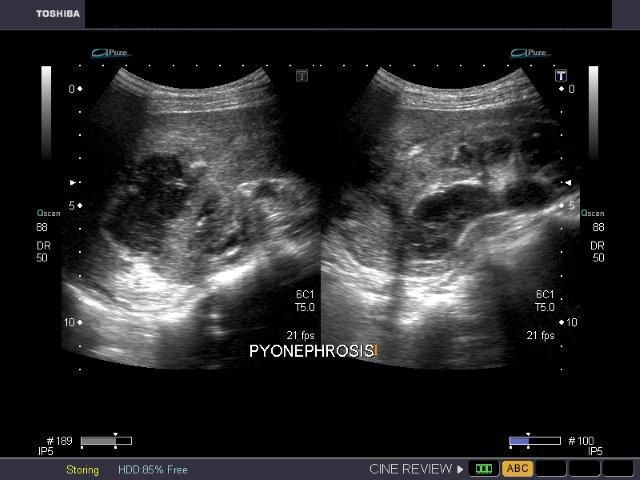

Pyonephrosis

This patient showed a right upper ureteric calculus with obstructive changes in the proximal part of the right ureter and pelvicalceal dilatation. In addition, the right kidney also showed particulate debris within the dilated collecting system with breach of the upper pole of right kidney a large hypoechoic collection around this region suggestive of renal abscess formation. These ultrasound images suggest right pyonephrosis with abscess of right kidney. Chronic obstruction caused by the right ureteric calculus (see ultrasound image in top row- left), is the cause of this pathology, in this case. (Images are courtesy of Gunjan Puri, MD, India).

Case-2: Pyonephrosis with ureteric calculus

Ultrasound images of the right kidney show fluid-debris levels in the calyces as well as the pelvis of the right kidney. The pelvicalyces show moderate dilatation. There is also evidence of right hydroureter extending down to the lower third. Here a right ureteric calculus is seen (1.1 cms. in size). Final diagnosis- right pyonephrosis caused by right ureteric calculus. Ultrasound images are courtesy of Dr. Ravi Kadasne, MD, UAE.